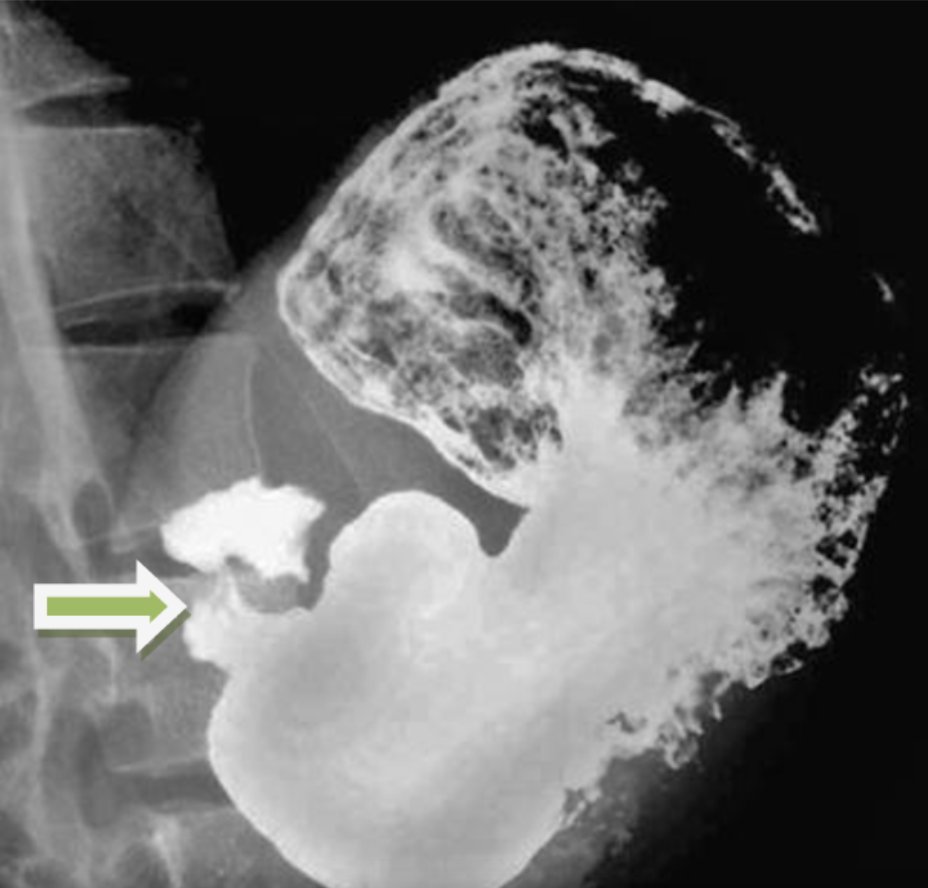

Gastric outlet obstruction (GOO).

Anatomically, mechanical obstruction can be at distal stomach, pyloric channel, or duodenum and can be intrinsic or extrinsic to the stomach.

👉Benign: Early satiety (53%) and bloating (50%).

Example: Peptic ulcer disease (resulting in a stricture of stomach/duodenum),

👉Malignant: Pain, vomiting, weight loss, and malnutrition.

Distal gastric cancer, common, 35 %.

👉20% of patients with pancreatic cancer develop GOO.

Labs:

Electrolyte abnormalities, and dehydration, including hypochloremic metabolic alkalosis & hypokalemia.

Credit:

National Center for Biotechnology Information

Radiopaedia

RSNA.org/Journals.

2/nImage